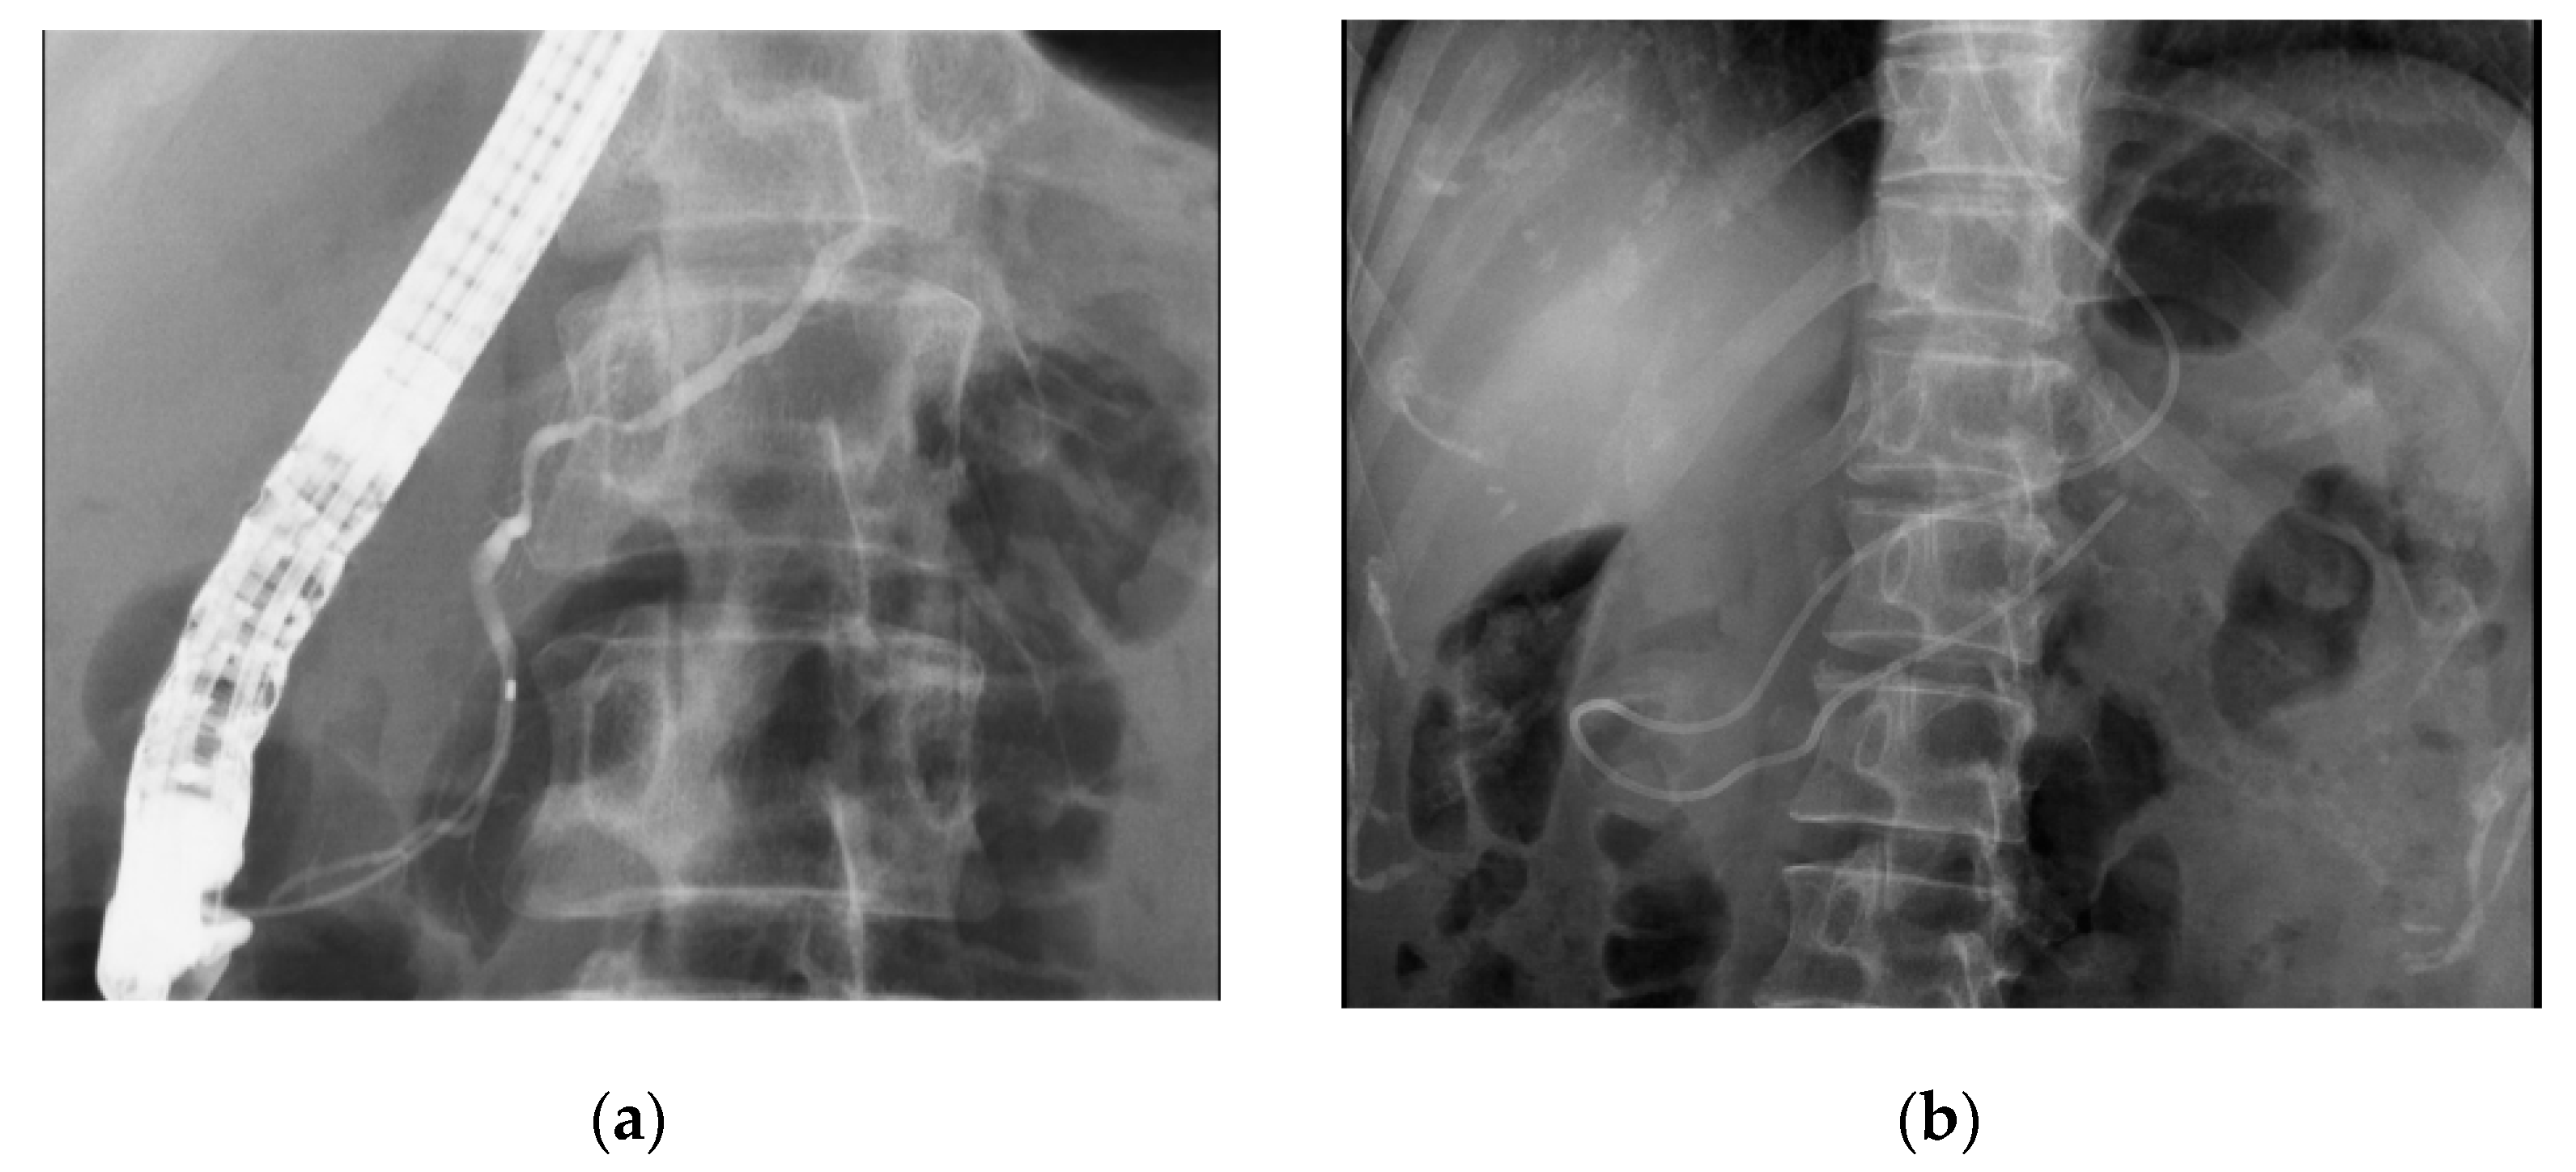

- Hanada, K.; Minami, T.; Shimizu, A.; Fukuhara, M.; Yano, S.; Sasaki, K.; Koda, M.; Sugiyama, K.; Yonehara, S.; Yanagisawa, A. Roles of ERCP in the Early Diagnosis of Pancreatic Cancer. Diagnostics 2019, 9, 30. [Google Scholar] [CrossRef] [PubMed]

- Izumi, Y.; Hanada, K.; Okazaki, A.; Minami, T.; Hirano, N.; Ikemoto, J.; Kanemitsu, K.; Nakadoi, K.; Shishido, T.; Katamura, Y.; et al. Endoscopic ultrasound findings and pathological features of pancreatic carcinoma in situ. Endosc. Int. Open. 2019, 7, E585–E593. [Google Scholar] [CrossRef]